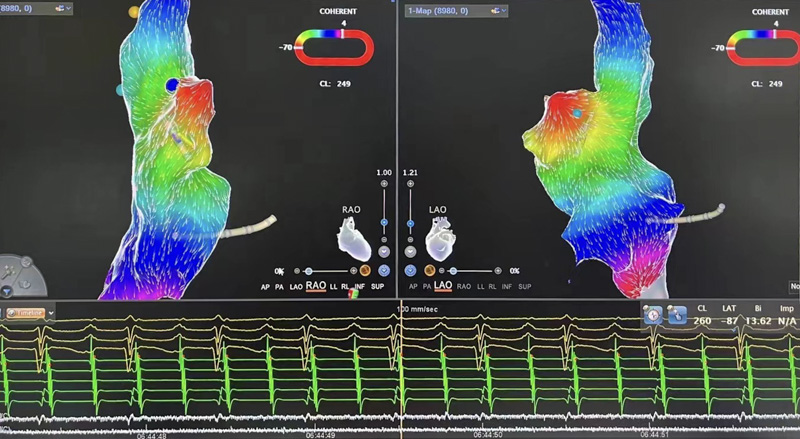

▲術中測標

介入室內,心血管內科電生理團隊開始為患者進行心電生理檢查,在三維系統指引下行激動標測提示心律失常起源于右心耳根部。右心耳是右心房的盲端,非常菲薄,大約只有1-2mm,附近有竇房結、上腔靜脈等重要結構,在此處消融,有心臟穿孔、損傷竇房結導致心臟停搏等風險。